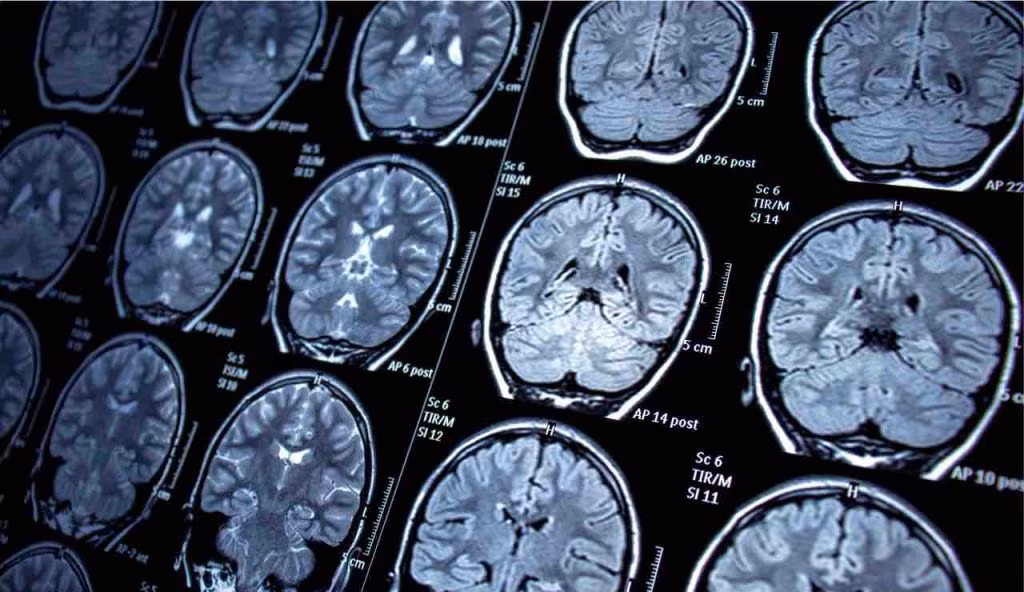

Lo studio pubblicato su “JAMA Neurology”, descrive l’uso di MELD Graph per rilevare le FCD in un ampio campione di pazienti. Con cui i ricercatori hanno analizzato i dati della risonanza magnetica di 1185 partecipanti (inclusi bambini e adulti), provenienti da 23 centri di epilessia siti nel mondo. Il set di dati, comprendeva 703 pazienti con FCD, e 482 persone sane: set stato utilizzato per addestrare l’intelligenza artificiale di MELD Graph, a riconoscere le lesioni cerebrali sottili, le quali possono sfuggire all’occhio umano.

MELD Graph è uno strumento avanzato di intelligenza artificiale, che analizza le immagini di risonanza magnetica cerebrale, per rilevare anomalie strutturali. E utilizzando algoritmi sofisticati, riesce a identificare anche le lesioni più difficili da vedere, come appunto le FCD. Un sistema che può quindi supportare i radiologi nel loro lavoro quotidiano, riducendo il rischio di errori, e aumentando la precisione nella diagnosi.